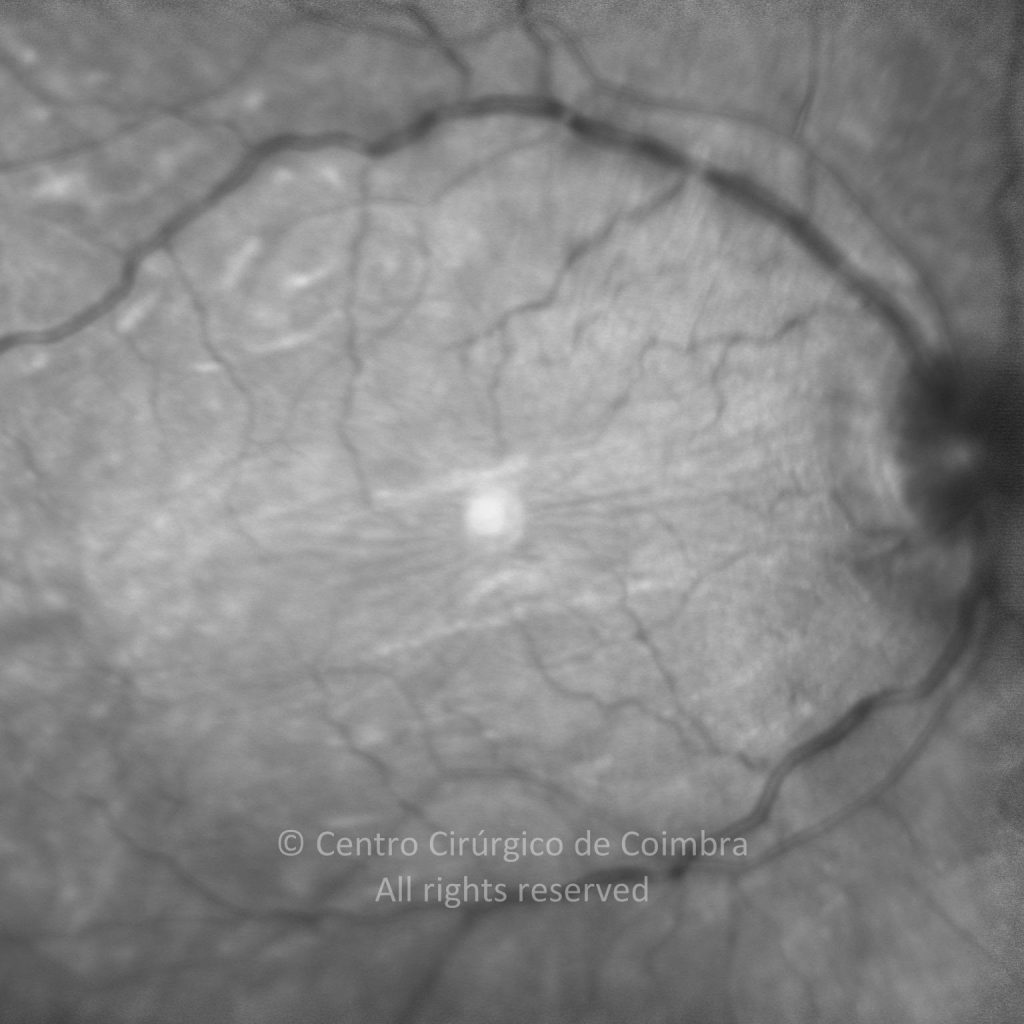

Paciente de 37 años con traumatismo contundente y ruptura del globo ocular. Presenta ruptura esclero-uveal, hifema, hemovítreo, desgarro periférico y temporal de la retina, hemorragias subretinianas y múltiples desprendimientos serosos.

MAVC: 20/25 OD, nueve años después de las cirugías (sutura escleral de la desinserción del músculo recto externo, vitrectomía posterior y fotocoagulación láser en el borde del desgarro retiniano, desprendimiento de retina inferior con proliferación vitreorretiniana y líquido subretiniano con algo de sangre; peeling de la membrana epirretiniana y maculorrexis de la MLI).